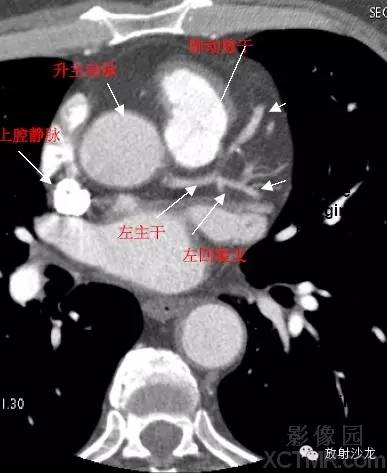

A.Aorta-Ascending Aorta升主动脉

SVC –Superior Vena Cava上腔静脉

PA -Pulmonary Artery肺动脉

LMA -Left Main Artery冠状动脉左主干

LCX -Left Circumflex Artery左回旋支